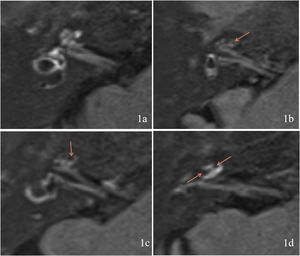

Evaluation of EHThe MRI results were classified according to the degree of EH using the criteria described by Gürkov et al.8 in 2011. Four scales were used for cochlear EH: Scale 0 (none hydrops, no enlargement of the endolymphatic space is noted in the cochlea and vestibule, and the perilymphatic space is clearly visible) (Fig. 1a); Scale 1 (mild hydrops, the endolymphatic space is enlarged with hypointensity bulging into the perilymphatic space with hyperintensity) (Fig. 1b); Scale 2 (marked hydrops, the endolymphatic space is enlarged, the scala media is convex to the scala vestibuli, and the perilymphatic space is semicircular) (Fig. 1c); and Scale 3 (extreme hydrops, the endolymphatic space is severely dilated, the scala media continues to be convex to the scala vestibuli, and the perilymphatic space is compressed into a flattened line) (Fig. 1d). Vestibular EH was classified into three degrees by calculating the ratio of the area of the endolymphatic space to the total area of the endolymphatic and perilymphatic spaces (R-value), with R ≤ 1/3 for Grade 0 (no hydrops) (Fig. 2a), 1/3 < R < 1/2 for Grade 1 (mild hydrops) (Fig. 2b), and R ≥ 1/2 for Grade 2 (significant hydrops) (Fig. 2c). All imaging results were evaluated by two specialized radiologists. Inconsistent results were resolved by consulting a senior radiologist.